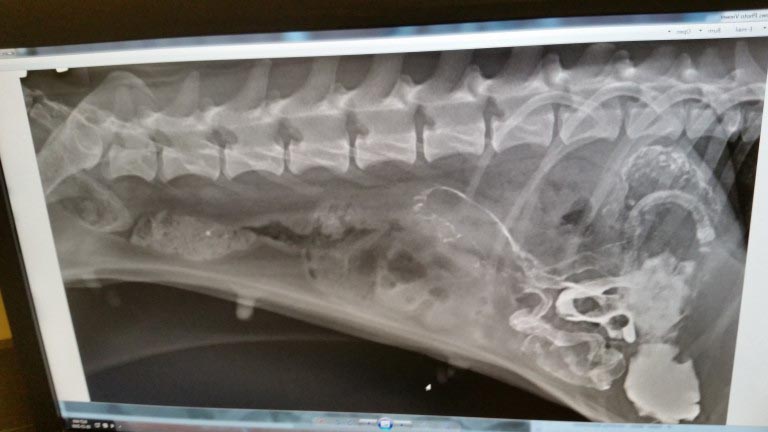

▼獸醫發現這隻小狗不是簡單的腸胃不適,而是腸梗阻,需要做手術。原po沒想到小狗的病情這麼嚴重,雖然治療費用非常高,但他並沒有猶豫。獸醫從狗狗的腸道裡取出了一些垃圾,有塑膠袋、布條等等,應該是狗狗流浪期間餓到不行時吃下去的。